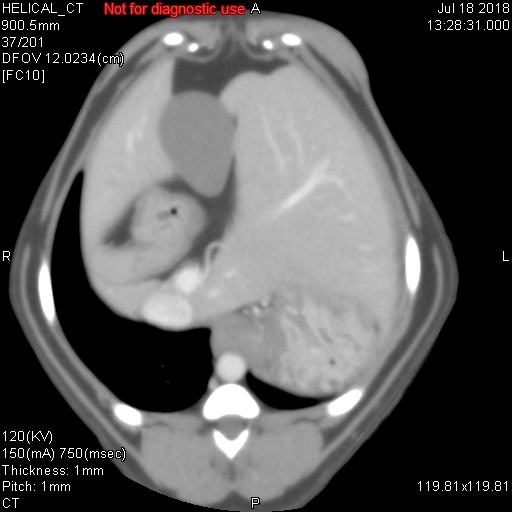

上記に載せました各写真ですが、CT検査で様々な条件で撮影した同一臓器(肝臓/胆嚢/胃/十二指腸/門脈/後大静脈/大動脈/肝動脈)です。CT検査では、そのまま撮影するプレーン、造影剤を使用する動脈相・門脈相・平行相がありますが、上記写真がどれかわかりますでしょうか??

シンプルに、一番上がプレーンです。臓器のシルエットくらいしかわかりません。その次が動脈相で、中央にピョろっとある肝動脈や背骨側にある太い血管(大動脈)が白くはっきりと写ります。また薄っすらと肝臓内にも多くの動脈がありますので、チラチラと動脈だけが見えてきます。3番目が門脈相といって肝臓の外にある門脈が白く際立ち、さらには肝臓内にある門脈(門脈枝)まで白くキレイに写ってきます。そして最後が平行相ですが、これは造影剤が通過して結構時間が経過した際の写真ですが、例えば具合が悪い臓器だと造影剤が抜けきるのが遅いため、時間が経過しているにもかかわらず造影剤がまだ残ってしまったりしますので、そのような際の評価に活かされます(あと悪性腫瘍など癌なども同じような見え方をします)。

造影剤を投与したあと20秒経過したときに撮影するのが動脈相、40秒が門脈相、120秒が平衡相といい、時間経過でCTスキャンを行って、様々な条件のもとで画像は分析されていきます。あと細かいですが、とある数字を設定して、その数字に達したらCTスキャンが開始されるなど、撮影方法にもいろいろあります。ただ単純にCTスキャンをしているだけではなく、造影剤を使用したり、投与時間を細かく設定したり、さらにいろいろな条件下で画像を比較して、最適かつ確実な画像診断を行っているのが、CT検査なのです。